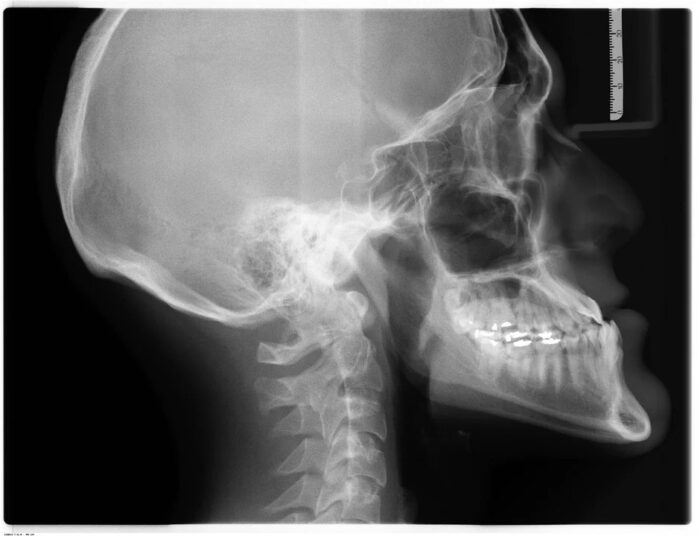

Underbite and Overbite Correction Without Surgery

Speak to your orthodontist near me about your oral concerns regarding overbites or underbites. There are a lot of treatments available for you that do not involve surgery. Underbite correction without surgery – Underbite jaw correction without surgery Getting underbite correction without surgery may seem like a tall order for your Miami Shores orthodontist for…